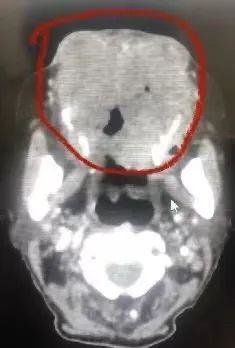

患者CT图,治疗前

据张旭阳介绍,老人刚来时,面部的肿瘤直径已经超过10厘米, 重量达到了1公斤左右,很快就要压迫到影响呼吸。